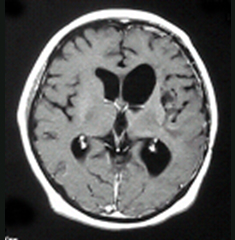

ところが、最近少しずつ状況が好転してきました。平成18年、欧米を始め世界各国ではすでに悪性神経膠腫の標準薬として使用されていたテモゾロミドが、我が国でも承認されました。この抗癌剤は飲み薬ですが従来の注射薬と比べても治療効果が高く、2年生存率を3倍に伸ばすという効果が実証されています。図1の患者さんは、手術・放射線や他の薬剤を使用した化学療法でも腫瘍の進行を全く止めることが出来なかったのですが、テモゾロミドを4コース使用した後に、腫瘍が完全に消失しました。この患者さんはその後3年間にわたって再発がありません。

図1:悪性脳腫瘍に対するデモゾロミドの効果

4コース終了後